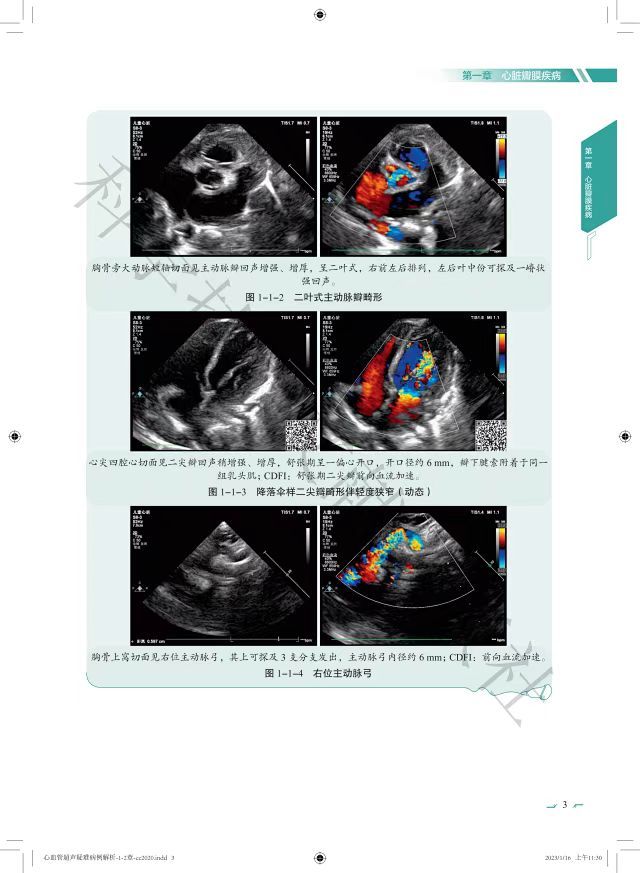

本书由四川省医学科学院•四川省人民医院(电子科技大学附属医院)心血管超声及心功能科主任尹立雪教授携团队共同编撰,以百余个心血管疑难少见案例为主线,从病史、辅助检查、超声心动图、术中所见、鉴别诊断、最终诊断等方面多角度深入分析、讨论,并概括总结了经验/教训、病例启示,力图从不同角度全面展示心血管超声专家在工作中接触到疑难少见病例时积累的诊疗心得。

书中精心挑选的超声图像,详细的病例解读,可使读者身临其境地融入到疑难少见疾病诊治的各个环节,并从笔者的宝贵经验中获得启发,不仅可丰富临床思维,提升个人能力,还可弥补因工作环境不同所带来的对疾病认知的差异,助其适应心血管超声的飞速发展,在心血管超声领域脱颖而出。